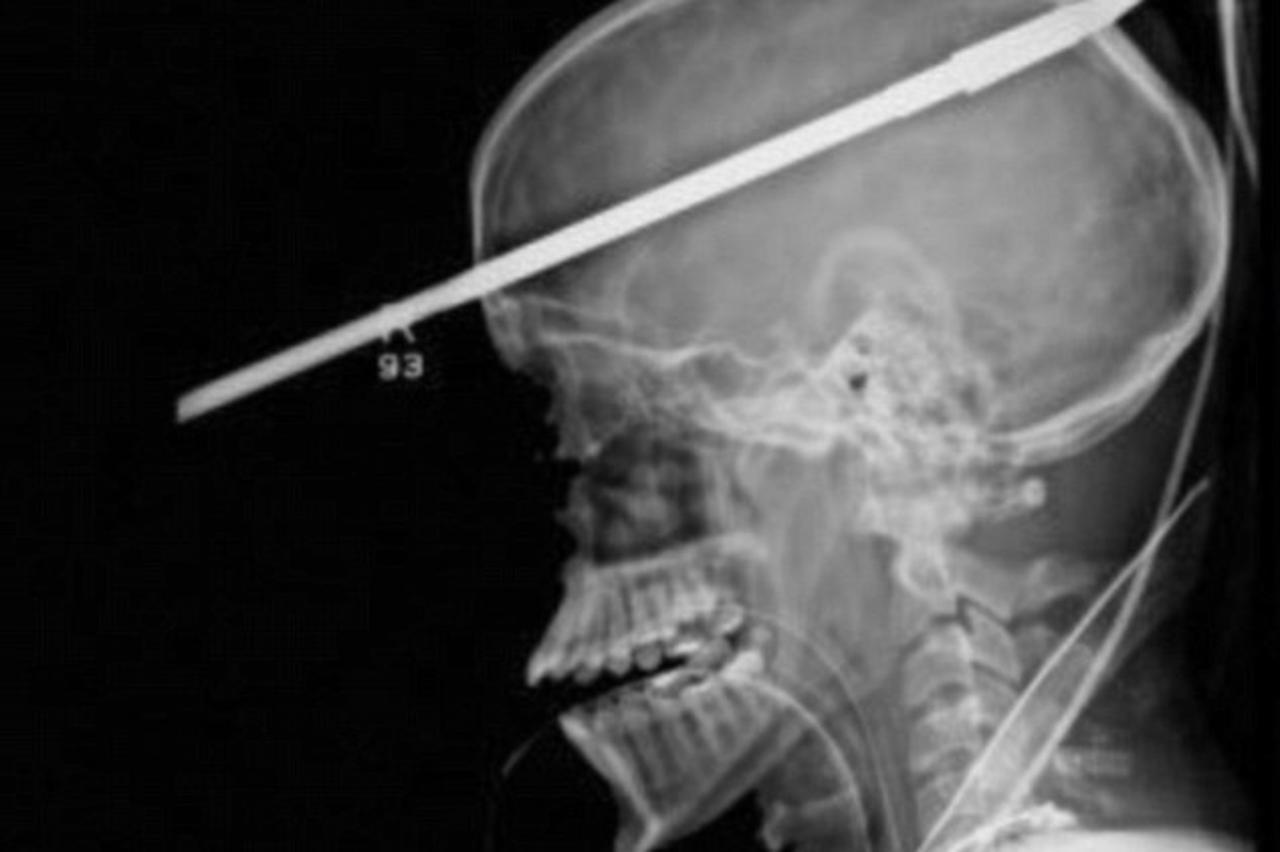

bizarna nesreća Dječak (16) preživio nakon što ga je u glavu pogodio harpun Operacija vađenja harpuna iz dječakove glave trajala je tri sata. Stanje mu je i dalje teško, ali je stabilan